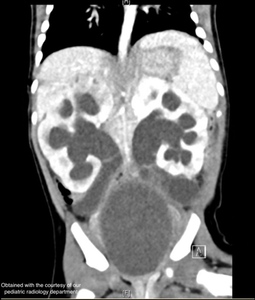

Due to severe dehydration, the patient was admitted to the pediatric intensive care unit (PICU) and started on intravenous fluids. Meanwhile, a rapidly growing mass was observed in the lower mid-abdomen. An ultrasound scan showed a massive cystic mass in the abdomen with severe urinary obstruction. A subsequent CT scan revealed a markedly enlarged renal pelvis with reduced renal perfusion, bilateral megaureters, and a 9 x 5 cm cystic septated structure. (figure 1). The outer genital showed normally developed labia but no vaginal entrance. An exploratory laparotomy revealed an enlarged and protruding uterus. The ovaries and fallopian tubes were normally developed. Following uterine incision through the vagina, over 100 mL of purulent fluid was drained, and a Redon drain was placed. Immediately after drainage, urine began flowing through the inserted bladder catheter and intraoperative ultrasound showed a decrease in renal pelvic calyx dilatation. Uterine drainage analysis demonstrated a high cell count, mainly granulocytes. Uterine drainage grew Streptococcus anginosus, which led to the diagnosis of pyometra. In addition, urine culture grew Streptococcus anginosus and Escherichia coli.